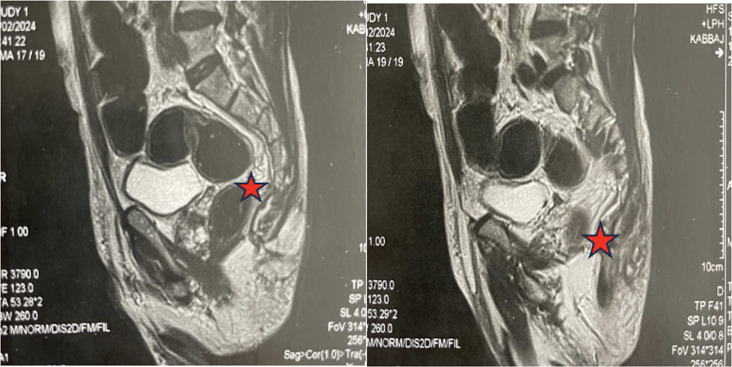

Tuberculosis (TB) is a preventable and usually curable disease but remains a major health problem worldwide, particularly in developing countries. TB of the lumbosacral junction is rare and occurs in only 1-2% of all cases of spinal TB. Moreover, isolated sacrococcygeal TB is extremely rare. We present a case of a 64-year-old patient with a history of diabetes who presented with chronic back pain and cough. Physical examinations revealed a perianal fistula and left elbow joint arthritis. The patient is diagnosed with disseminated TB with coccygeal involvement. Diagnosis was achieved non-invasively using Xpert MTB/RIF, confirming Mycobacterium tuberculosis infection. The patient experienced complete resolution of symptoms following the commencement of anti-TB therapy. We highlight the importance of this case due to the rare coccygeal localization of TB in an immunocompetent patient, diagnosed through non-invasive means.